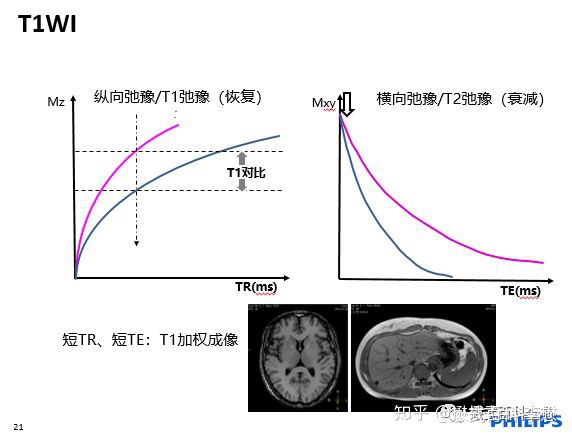

T1加权像(T1WI):主要是反映组织之间T1差别的图像,也就是主要反映组织之间纵向弛豫差别的图像;

短TR,短TE,是T1加权像;

TR越长,组织的纵向弛豫恢复越彻底,那么组织之间的纵向弛豫差异(T1)的差异被削弱,所以要得到T1差异,TR不能长;TE越长,代表回波时间越长,组织在横向之间的弛豫差异会被拉大,组织的T2差异会越大。所以,要削弱T2差异,就要让TE短。所以,为什么短TR,短TE,突出的是组织的T1对比。

T1越长,在T1WI中,组织的信号强度越低,反映的是图像越黑;

T1越短,在T1WI中,组织的信号强度越高,反映的是图像越白。

脂肪组织是一种短T1,稍短T2的组织,这个是脂肪组织的特质参数。

如上图所示,是一个头颅的T1WI,非常常见。我们用前面所学的知识。液体(脑脊液)是长T1的,在T1WI中,应该是低信号,是暗的,所以图中,脑脊液是黑色的;而脂肪组织是短T1的,在T1WI中,是高信号,是白的,所以图中,头皮脂肪是亮的。